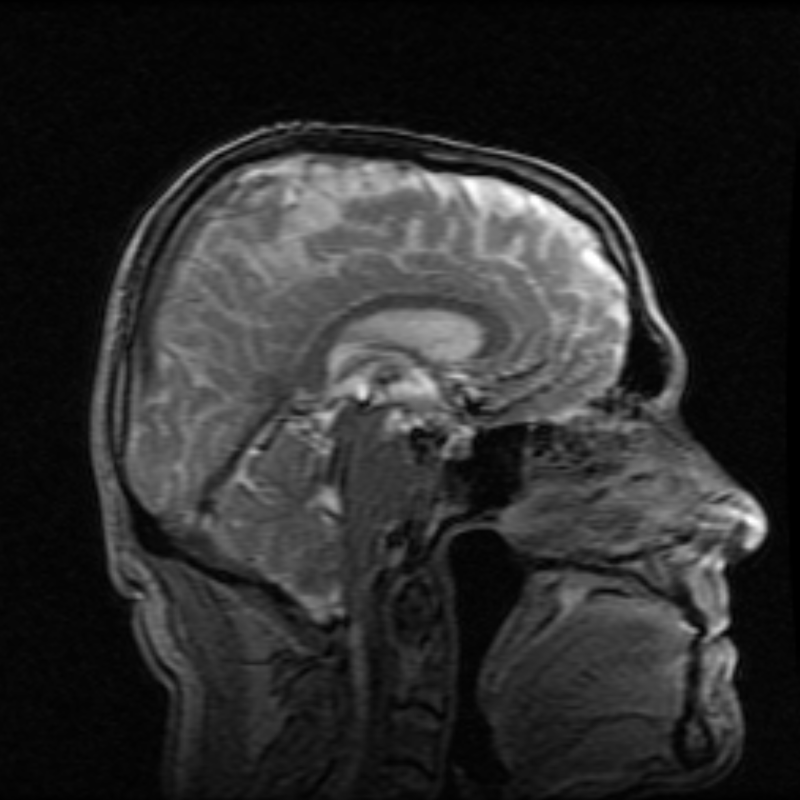

Cognitive Effects of CTE in NFL Players

Lights, Camera, Action: Analyzing fMRI Data through Voxel Searchlights and Representational Similarity Analysis to Identify Local Cognitive Representations in the Brain

SARS CoV-2 Effects on Alzheimer’s Pathogenesis